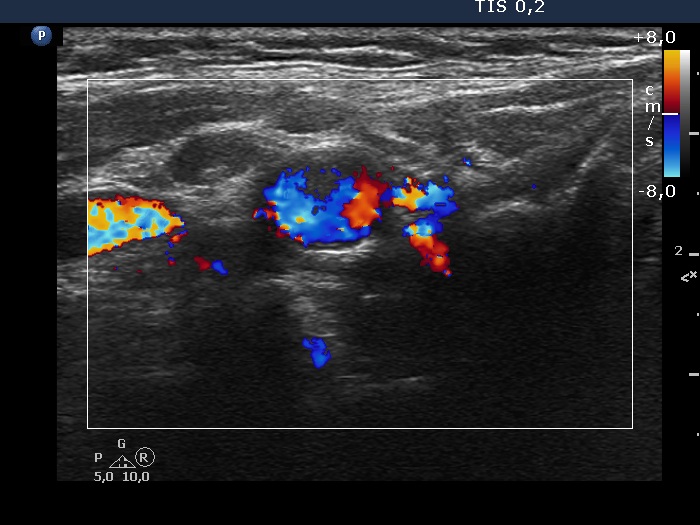

Intranodular hyperechogenic figures - case 2174 (ultrasonographic picture 8)

Left lobe, another transverse scan, color Doppler node. The node presents a regular hilum and lacks vascularization.